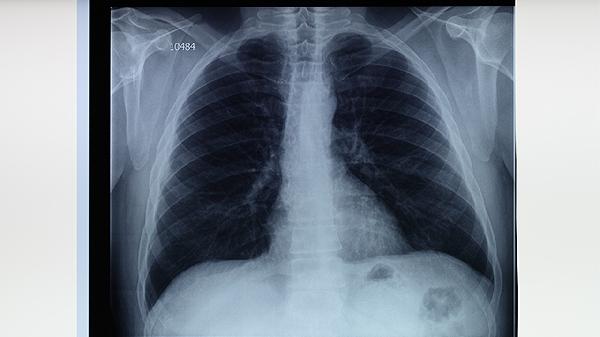

肺结核可能会导致肺坏死。肺结核是由结核杆菌感染引起的呼吸系统传染病,如果患者病情严重、治疗不及时或治疗方法不当,则可能导致肺组织受损和坏死。 一、原因 1.病情严重:肺结核是一种严重的疾病,如果不

区分感冒咳嗽和肺结核咳嗽可从病程、伴随症状、痰液特征等方面综合判断。感冒咳嗽多由病毒感染引起,病程较短;肺结核咳嗽由结核分枝杆菌感染导致,病程迁延且可能伴随全身症状。 感冒咳嗽通常急性起病,1-3天

2025-11-12 04:47:06